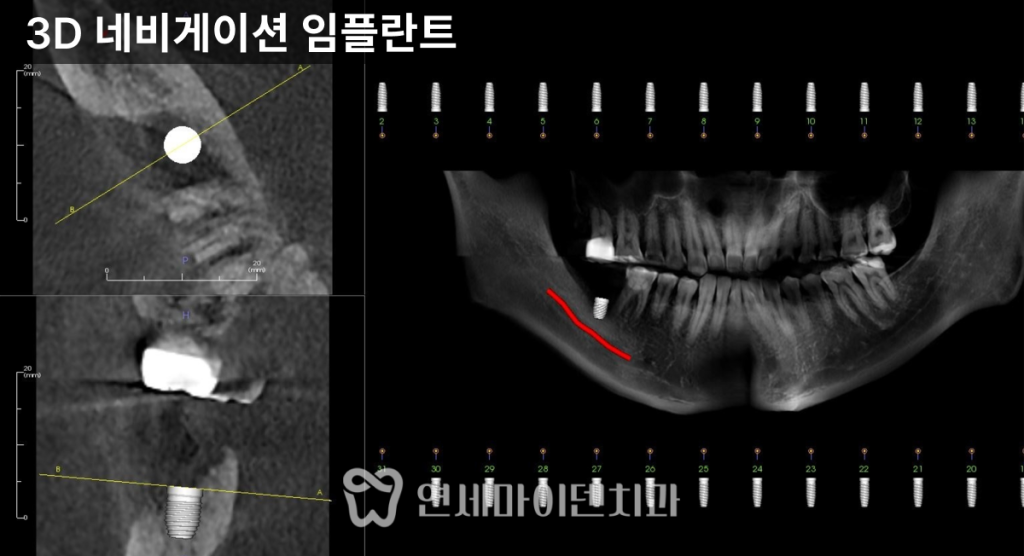

✔ 1. 식립 위치

임플란트를

정확한 위치와 각도로 식립해야 합니다.3D CT 분석과

네비게이션 기반 모의 수술을 통해

센터에 정확히 심는 과정이 중요합니다.위치가 어긋나면

보철 설계가 어려워지고

음식물 끼임이 증가합니다.